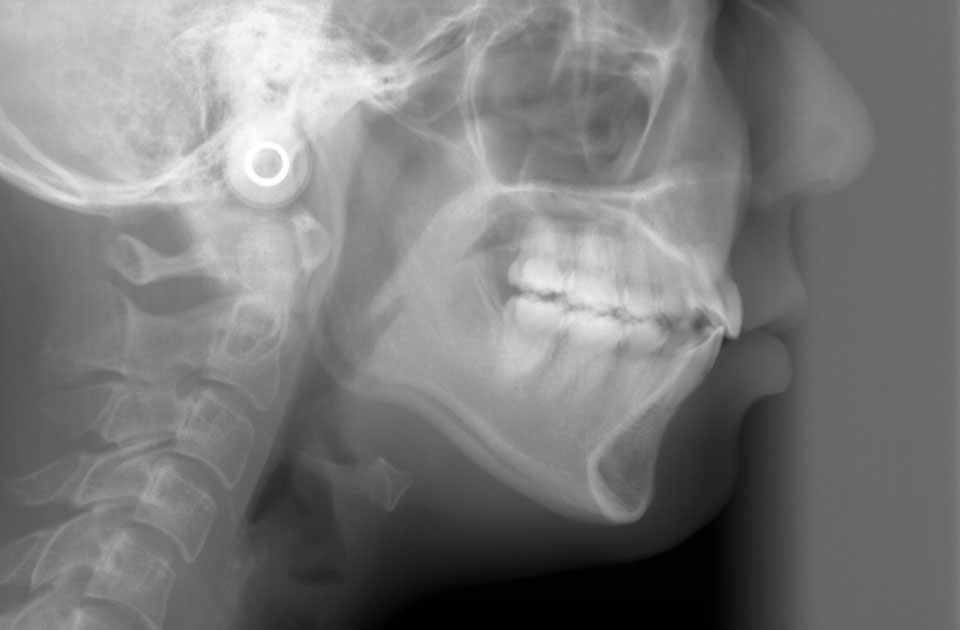

矯正前 レントゲン

主訴 前突感、口が閉じずらく前歯で物が咬めない。

年齢 20代

治療法 上下顎マルチブラケット装置

抜歯の有無 上顎左右側第一小臼歯、下顎左右側第一小臼歯

治療期間 1年10ヶ月